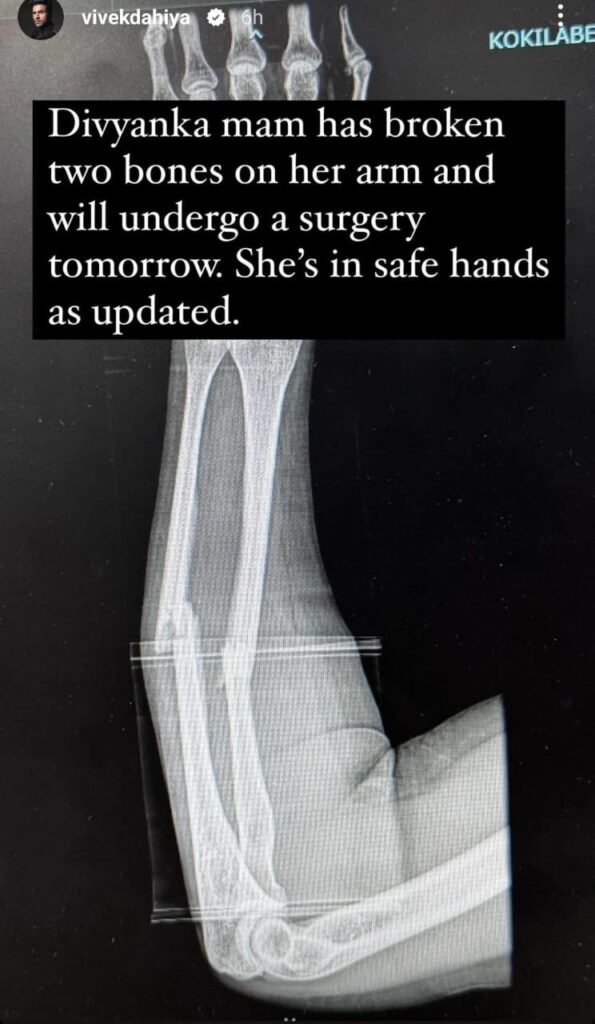

Vivek shared a photo of Divyanka’s X-ray on Instagram, revealing that she sustained a fractured arm in the incident. He further informed that she is set to undergo surgery on April 19, Friday.

In an Instagram story posted on April 18, Vivek conveyed, “Divyanka mam has broken two bones on her arm and will undergo surgery tomorrow. She’s in safe hands as updated.”